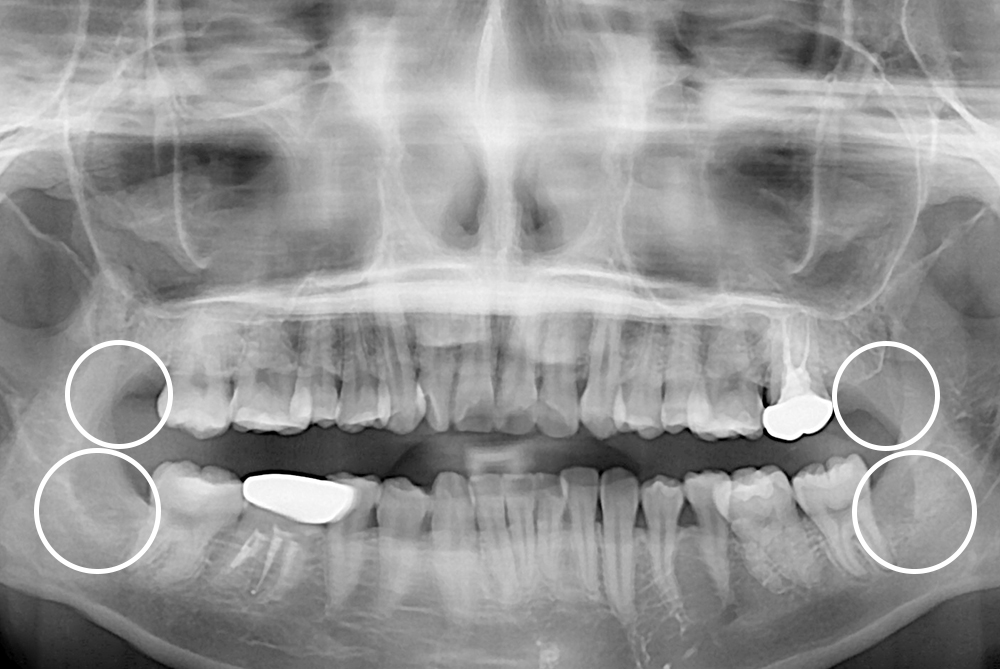

[사랑니] 매복 사랑니 발치

치료후 : 2019-05-10

세종치과는 구강악안면외과학 박사이신 원장님이 발치하는 치과입니다.